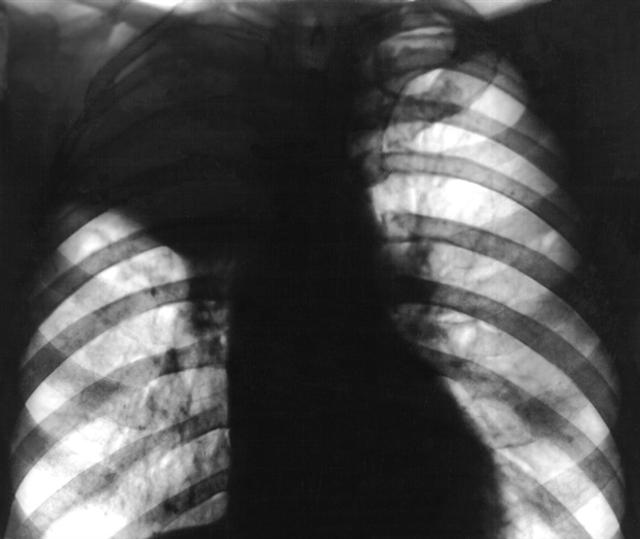

Рис. 2а). Рентгенограмма грудной клетки при ателектазе верхней доли правого легкого (прямая проекция): верхняя доля правого легкого уменьшена в объеме, гомогенно затенена.